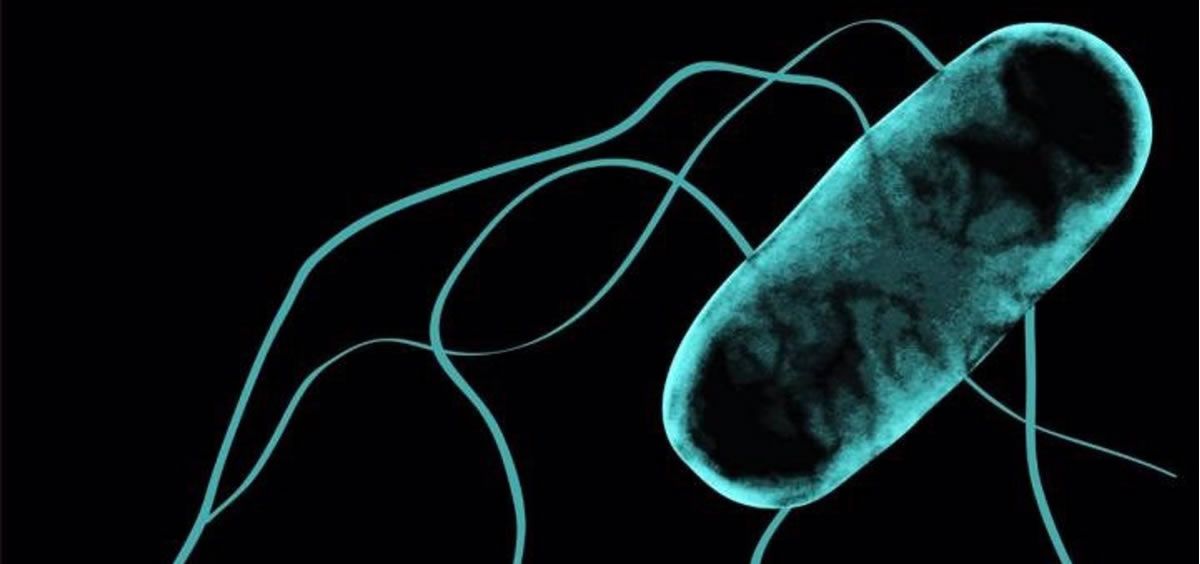

El Centro Europeo para la Prevención y el Control de las Enfermedades (ECDC) y la Autoridad Europea de Seguridad Alimentaria (EFSA) han publicado un informe en este sentido alertando de la resistencia a los antibióticos de las bacterias 'Salmonella' y 'Campylobacter', típicas de las intoxicaciones alimentarias.

La campilobacteriosis fue la zoonosis más notificada en la UE en 2020 y la causa más frecuente de enfermedades transmitidas por los alimentos. Las bacterias 'Campylobacter' de los seres humanos y las aves de corral siguen mostrando una resistencia muy alta a la ciprofloxacina, un antibiótico de fluoroquinolona, que se utiliza comúnmente para tratar algunos tipos de infección humana bacteriana.

Se han observado tendencias crecientes de resistencia contra la clase de antibióticos fluoroquinolonas en humanos y pollos para 'Campylobacter jejuni'. En la 'Salmonella Enteritidis', el tipo más común de 'Salmonella' en humanos, se observaron tendencias crecientes de resistencia a la clase de antibióticos quinolona/fluoroquinolona. En los animales, la resistencia a estos antibióticos en 'Campylobacter jejuni' y 'Salmonella Enteritidis' fue en general de moderada a alta.

Sin embargo, a pesar de las tendencias crecientes de resistencia contra ciertos antibióticos, la resistencia simultánea a dos antibióticos de importancia crítica sigue siendo baja para 'E. coli', 'Salmonella' y 'Campylobacter' en bacterias tanto de humanos como de animales productores de alimentos.